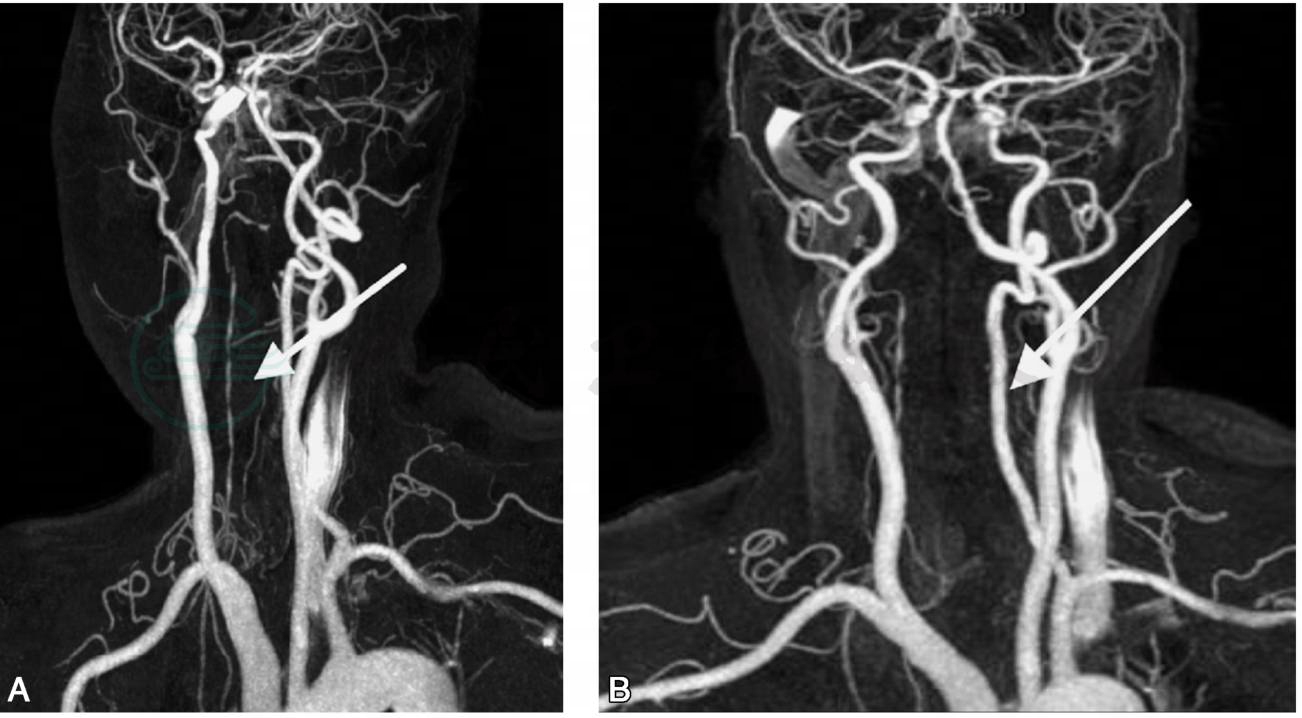

图2 头颈3DCE-MRA(2010年7月16日)

A.右侧椎动脉先天发育欠佳、细小、硬化颅内段近闭塞(箭头); B.左侧椎动脉管腔信号均匀,未见明显狭窄(箭头)